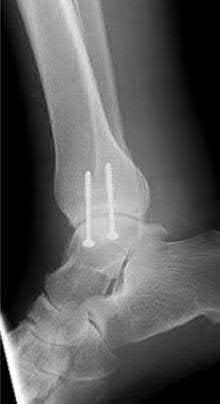

A 28-year-old male sustains a severe hyper-dorsiflexion injury to his ankle in a motor vehicle accident, resulting in a Hawkins Type III talar neck fracture. Which of the following arteries provides the predominant blood supply to the body of the talus, placing it at significant risk for avascular necrosis in this injury?

Explanation

The artery of the tarsal canal, which is a branch of the posterior tibial artery, provides the dominant blood supply to the talar body. In a Hawkins Type III fracture (talar neck fracture with subtalar and tibiotalar dislocation), the blood supply from the artery of the tarsal canal, the artery of the sinus tarsi, and capsular vessels are disrupted, leading to an avascular necrosis (AVN) rate approaching 100%.